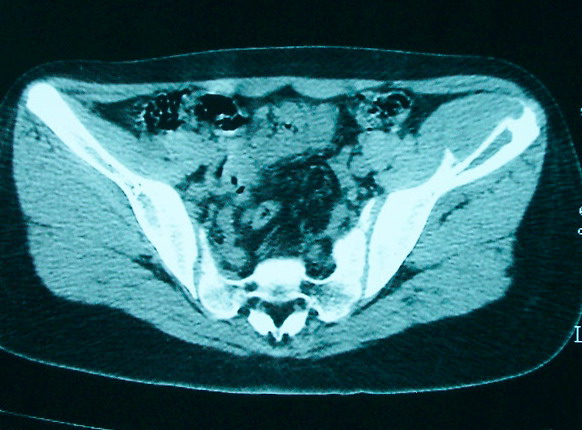

女 13岁 4月前有臀部肌肉注射史 3月前发热 最高体温38.5 2月前出现左髂骨疼痛 不剧烈能忍受 发热时高时低 按感冒治疗无好转 近日左髂骨疼痛加重 一星期前wbc 12.2 今日wbc9.5

左侧髂骨溶骨性骨质破坏,骨皮质侵蚀,灶周可见软组织肿块,支持考虑骨肉瘤可能性大。

髓腔起源,弥漫性溶骨性骨质破坏并软组织肿块,膨胀不明显,无显著钙化及瘤骨,有骨膜反应,结合年龄考虑恶性,尤文氏肉瘤可能性大。

支持髂骨低毒性骨髓炎或骨结核:骨质破坏,髂腰肌明显肿胀,非长管状骨部位。

骨质破坏+增生+软组织肿胀提示骨髓炎